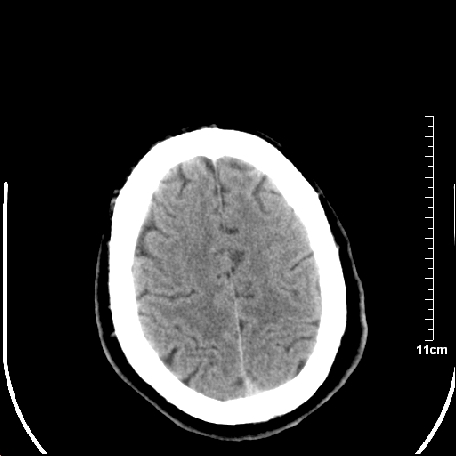

双侧外侧裂,左侧脑沟见高密度结节影,边清,还有鞍上池层面密度也高

靠,老年脑,没什么病。

都是血管。

脑血管硬化?高血红蛋白症?

高血红蛋白症可能

高血红蛋白症

高血红蛋白血征

基底动脉硬化迂曲。高血红蛋白血症。